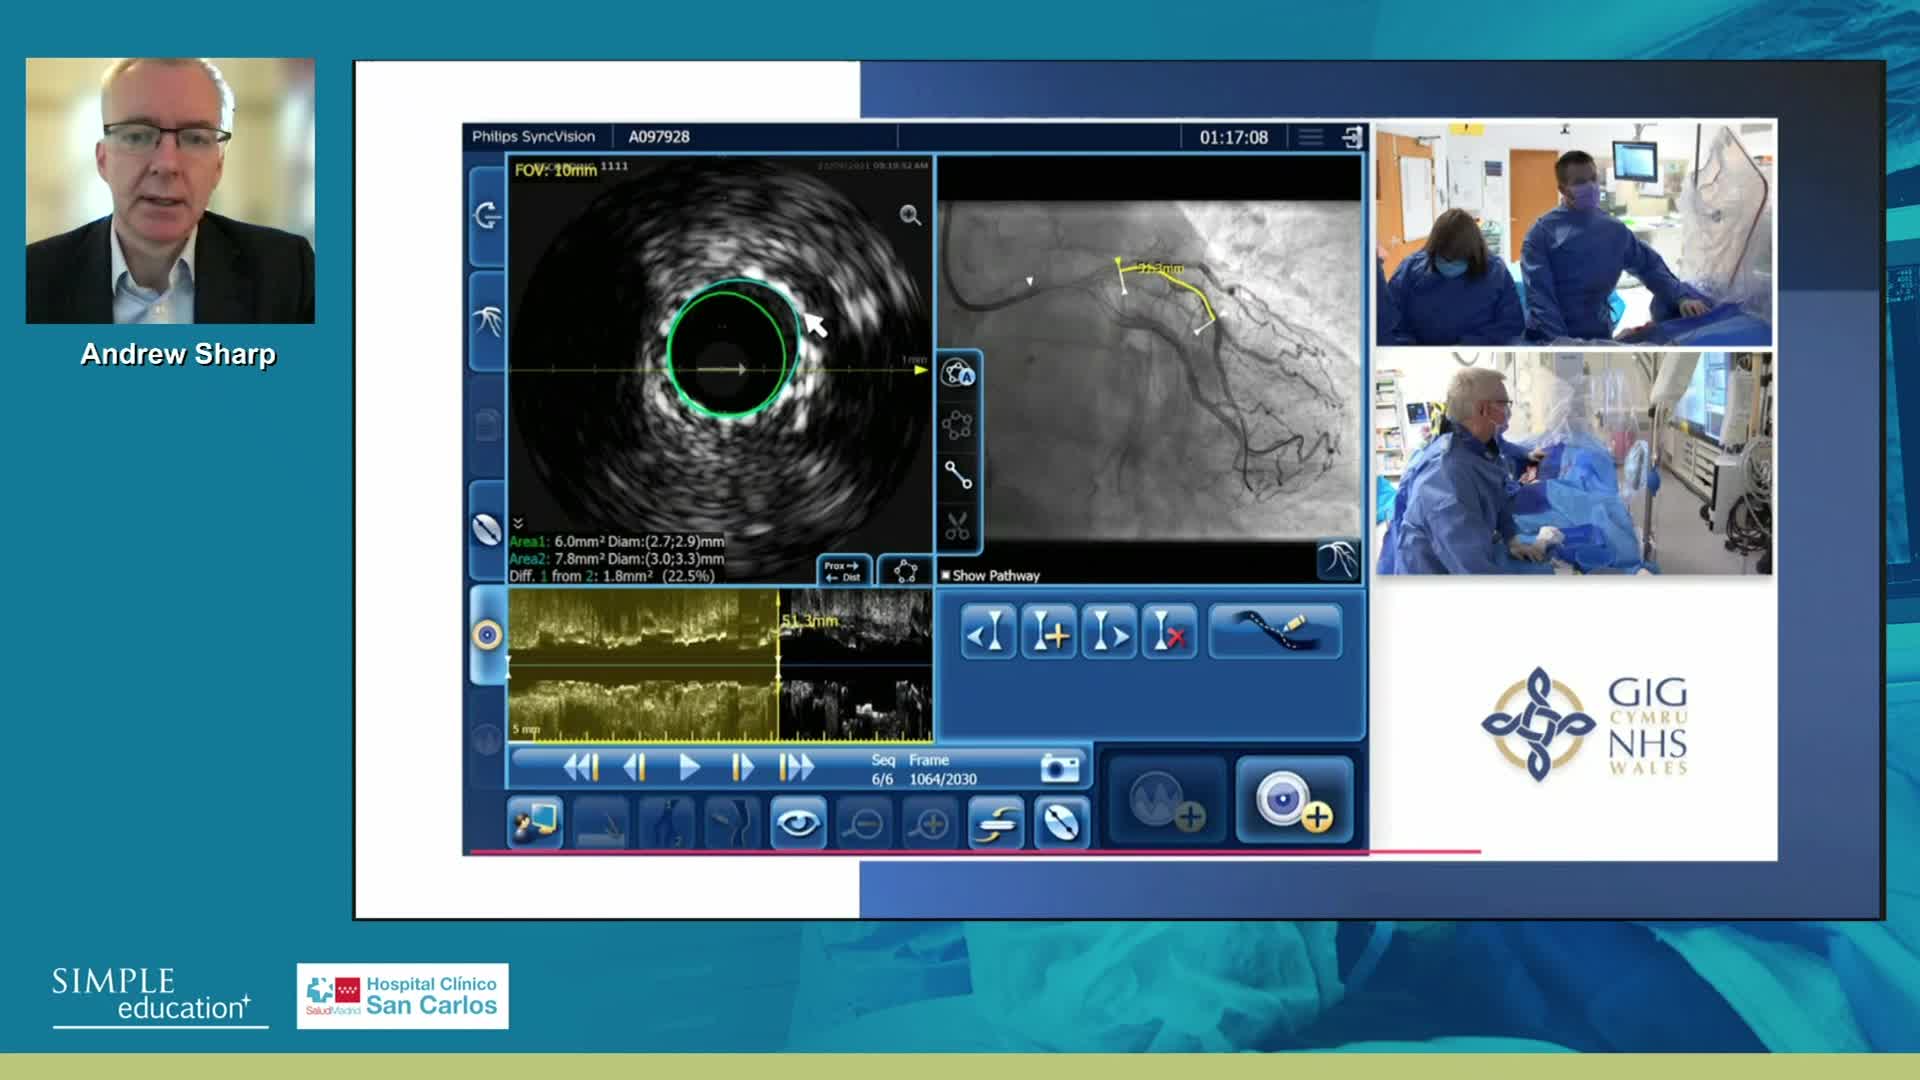

Understanding how SyncVision differs from other co-registration based technologies - Dr Justin Davies

How to perform good co-registration measurements using iFR and IVUS - Prof Carlo Di Mario

Using SyncVision Co-registration to distinguish between focal and diffuse coronary disease. - Prof Giuseppe Tarantini